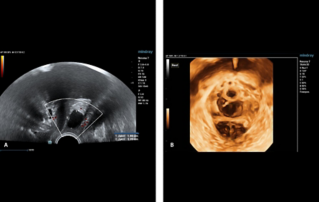

Female pelvic floor anatomy, which developed since the early 20th century, has had a variety of theories, including integral theory, three levels of vaginal support theory, "hammock hypothesis", and three-chamber system. Supporting structures such as pelvic floor muscles, fascia and ligament play an important role in maintaining the normal function of pelvic floor, among which levator ani muscle group is one of the most important supporting structures.